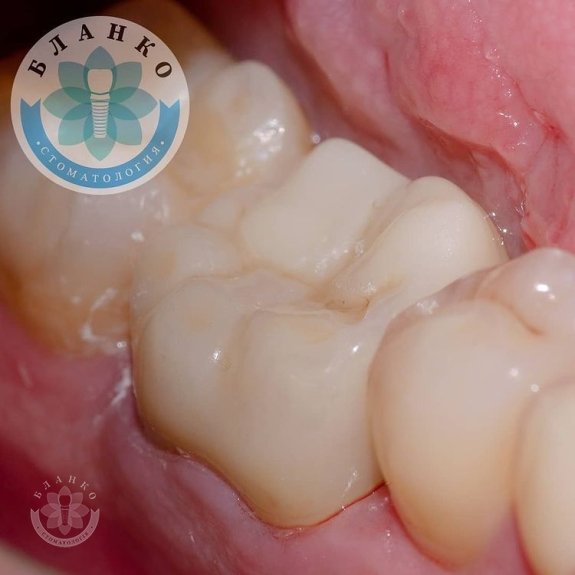

— сняты оттиски и изготовлена высокопрочная, гипоаллергенная и высокоэстетичная коронка из диоксида циркония.

✳️Итого, мы наблюдаем интересную ситуацию.

На примере этого клинического случая мы отчетливо видим, что экономить на своём здоровье нежелательно, потому что зуб — не туфель, в урну не выбросишь.